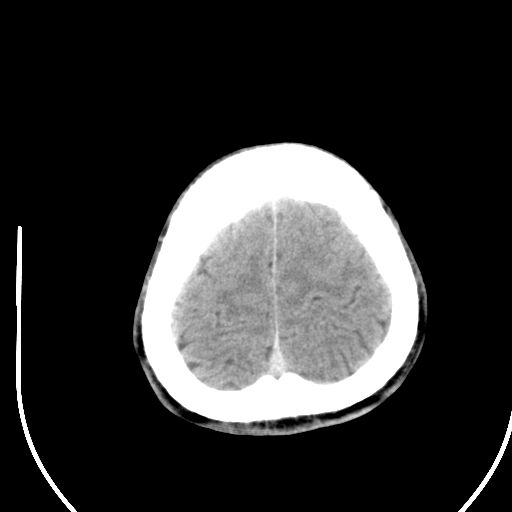

标题: CT28158:男,27Y。头痛数月,左顶叶血管瘤。 [打印本页]

标题: CT28158:男,27Y。头痛数月,左顶叶血管瘤。

海绵状血管瘤

考虑左顶叶海绵状血管瘤,建议mr检查。

左侧额叶海绵状血管瘤可能性大;建议行mri检查。

考虑血管畸形,因其周可见水肿,不除外感染性病灶。建议mri检查。